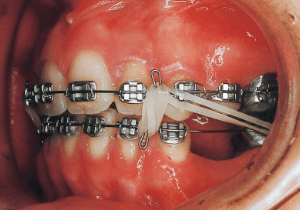

Extraction.

6 10-1-’85 at appliance replacement

Assessment and Management: Based on the pre-treatment condition (as assessed using models), the overjet and Class II molar relationship can be improved within the scope achievable by utilizing space created by extracting the maxillary left and right first premolars. Therefore, the treatment plan regarding tooth extraction would likely have been the same as that of the previous orthodontist. However, the progress of treatment over the past 10 months has not been entirely positive. Although it is unclear how these undesirable conditions arose, I determined they resulted from the destruction of the fixation and the influence of the tongue. I decided to continue treatment as is by rebuilding the mechanism.

The treatment progressed more favorably than anticipated, with the open bite and Class II malocclusion nearly resolved within five months of treatment initiation. However, discontinuing the use of rubber bands often resulted in an open bite.